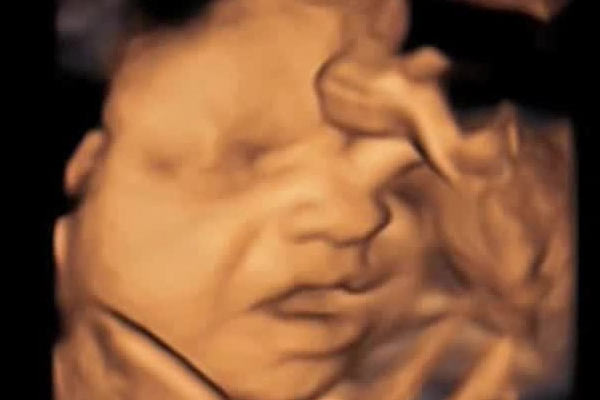

Kıbrıs'ta cenin operasyonu

Kürtaj zamanı geçmiş bebekleri kürtajla alan kadın doğum doktorunun çocuk ceninlerini eşiyle birlikte Girne bölgesindeki ormanlık alana gömdükleri tespit edildi. Polis tespitin ardından operasyon düğmesine bastı. Olayla ilgili zanlılar bugün mahkemeye çıkarıldı

5 ADET ÇOCUK CENİNİNİ ORMANA GÖMDÜLER

Girne Polis Müdürlüğüne yapılan bir ihbar sonucu tutuklanan çift ve sonrasında ormanlık alanda yapılan aramalarda 4-5 tane çocuk ceninine ulaşıldığı öğrenildi. Girne polisinde tutuklu bulunan doktor çiftin bugün mahkemeye çıkarıldı.